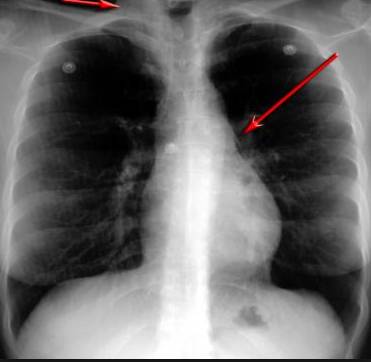

并且,因為呼吸系統結構復雜,在體檢時醫生很難通過一種檢測手段,判定早期患者的病情。

所以,很多人發現自己得了肺病,哮喘或其他呼吸系統疾病的時候,已經很危險了!多少人因此錯過最佳治療期!

這臺4D掃描儀

能讓醫生有一雙可以透視的眼睛

把整個肺部看得清清楚楚!

4D的! 高清透視!

使用這臺掃描儀,將直接把器官變成3D圖形!細微的毛細血管,幾毫米大的肺泡和支氣管,都將能看的一清二楚!

你的每一個氣泡,每一段支氣管,哪兒有病變都清清楚楚的將展示在醫生面前!

沒有這項新技術,醫生在做體檢的時候,很難通過一種測試斷定一個人是否有呼吸系統疾病。

可是現在他們不但能看到整個肺部的3維結構圖。還能看到空氣進入人體后的所有微小變動!